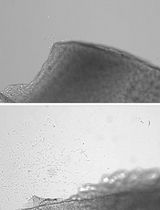

The goal of this protocol is to establish a procedure for cultivating stem cells on a fibrin carrier to allow for eventual transplantation to the eye. The ability to transfer stem cells to a patient is critical for treatment for a variety of disorders and wound repair. We took hair follicle stem cells from the vibrissae of transgenic mice expressing a dual reporter gene under the control of the Tet-on system and the keratin 12 promoter (Meyer-Blazejewska et al., 2011). A clonal growth assay was performed to enrich for stem cells. Once holoclones formed they were transferred onto a fibrin carrier and cultivated to obtain a confluent epithelial cell layer. Limbal stem cell deficient (LSCD) mice were used as the transplant recipient in order to test for successful grafting and eventual differentiation into a corneal epithelial phenotype.

Stem cells are widely used as a therapeutic tool, thus a means for delivery is essential. In fact, many researchers and companies are searching for the best way to deliver cells into the human body to optimize cell survival as well as integration into the host tissue. Injection methods have been widely used in animal models but often result in poor survival and integration. Techniques utilizing biomaterials and surgical devices are currently being employed. One technique that has been utilized to deliver stem cells is fibrin carriers. Fibrin gel is a degradable biopolymer that can adhere to native tissue allowing for cell attachment, migration and proliferation (Ehrbar et al., 2005). Fibrin gels have many advantages including biocompatibility, controlled degradation (Kjaergard et al., 1994; Sidelmann et al., 2000), uniform cell distribution and high cell seeding efficiency (Swartz et al., 2005). Fibrin gels have been utilized for treating skin burns (Pellegrini et al., 1999; Ronfard et al., 2000), junctional epidermolysis bullosa (Hirsch et al., 2017) and corneal damage (Pellegrini et al., 1997; Rama et al., 2010). The method described here uses a fibrin carrier to transplant hair follicle derived stem cells onto the ocular surface of a limbal stem cell-deficient mouse. Cell engraftment and differentiation was assessed for a 5-week period via fluorescent microscopy.